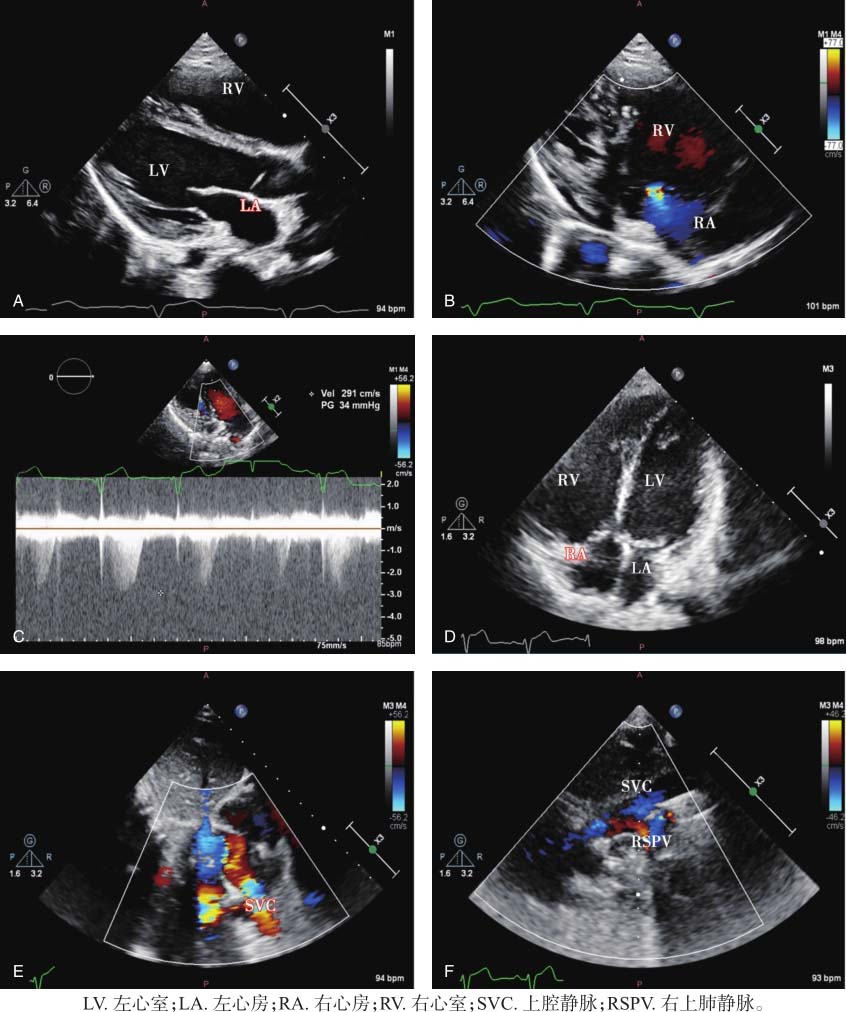

图21-1 患儿超声心动图表现

A.主动脉长轴切面显示右心房及右心室轻度增大,左心房及左心室内径大致正常;B.右心室流入道切面显示三尖瓣少量反流;C.三尖瓣反流频谱估测肺动脉压力增高;D.四腔心切面显示右心房及右心室增大;E.剑突下双心房切面显示上腔静脉回流增多;F.右侧高位胸骨旁切面显示右上肺静脉回流入上腔静脉,上腔静脉增宽,于此处可测量右上肺静脉距右心房入口的距离。

右心房及右心室轻度增大,左心房及左心室内径大致正常。室间隔与左心室室壁运动幅度正常,室壁收缩增厚率正常,右心室室壁厚约3mm,运动幅度正常。房室间隔无明显回声缺失。右上肺静脉未与左心房连接,开口于上腔静脉距右心房入口约18mm处,余肺静脉与左心房连接正常。三尖瓣环稍增大,前叶、隔叶对合略欠佳,余瓣膜未见明显异常。肺动脉明显增宽,主动脉弓降部无明显异常。

右上肺静脉血流经上腔静脉回流入右心房。未探及明显心房或心室水平分流。三尖瓣少量反流,估算肺动脉收缩压为40mmHg。见图21-1。